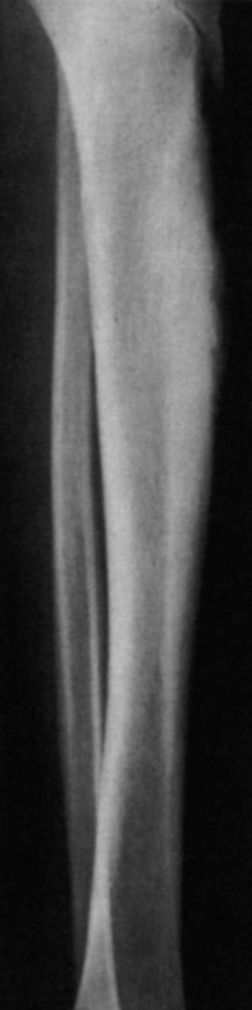

Na sífilis congênita tardia, um achado clássico é a sequela da periostite das diáfises e, com aumento da densidade na fase tardia com a aposição óssea, na perna causa o aspecto característico da “tíbia em sabre” (FIGURA 3). Outro achado clínico é a sinovite que acomete geralmente os joelhos (bilateral) com um aumento de volume, indolor e sem alterações radiográficas, também conhecido como articulações de Clutton.

FIGURA 3. Tíbia em sabre, encurvamento anterior e aumento da densidade pela aposição óssea após a periostite.